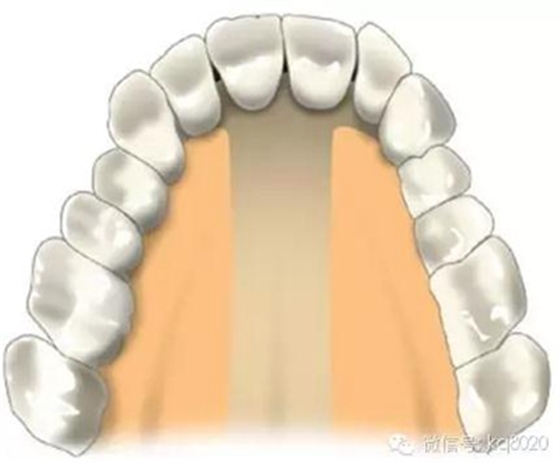

危險(xiǎn)因素:腭大動(dòng)靜脈及神經(jīng)出腭大孔后在距齦緣5-15mm距離向前直至切牙孔,植入部位不應(yīng)超過第二磨牙的遠(yuǎn)中,

以免傷及腭大孔;患者張口有限,會(huì)行成植入角度,容易觸碰牙根

植入位置和角度:牙根之間,冠狀面斜向下,避免過于水平未鉆入牙槽間隔,距離齦緣5mm處,

支抗釘與牙根成60°-70°角

大小:宜選用8×1.4mm支抗釘,并用彎機(jī)頭植入工具,以免支抗釘觸碰牙根

腭中縫兩側(cè)

危險(xiǎn)因素:腭中縫植入易穿破鼻竇;腭中縫尚未完全融合者,請(qǐng)離開中線5mm以上

植入位置和角度:垂直于骨面

大?。阂诉x用8×1.4mm支抗釘,并用彎機(jī)頭植入工具,方便垂直骨面進(jìn)入